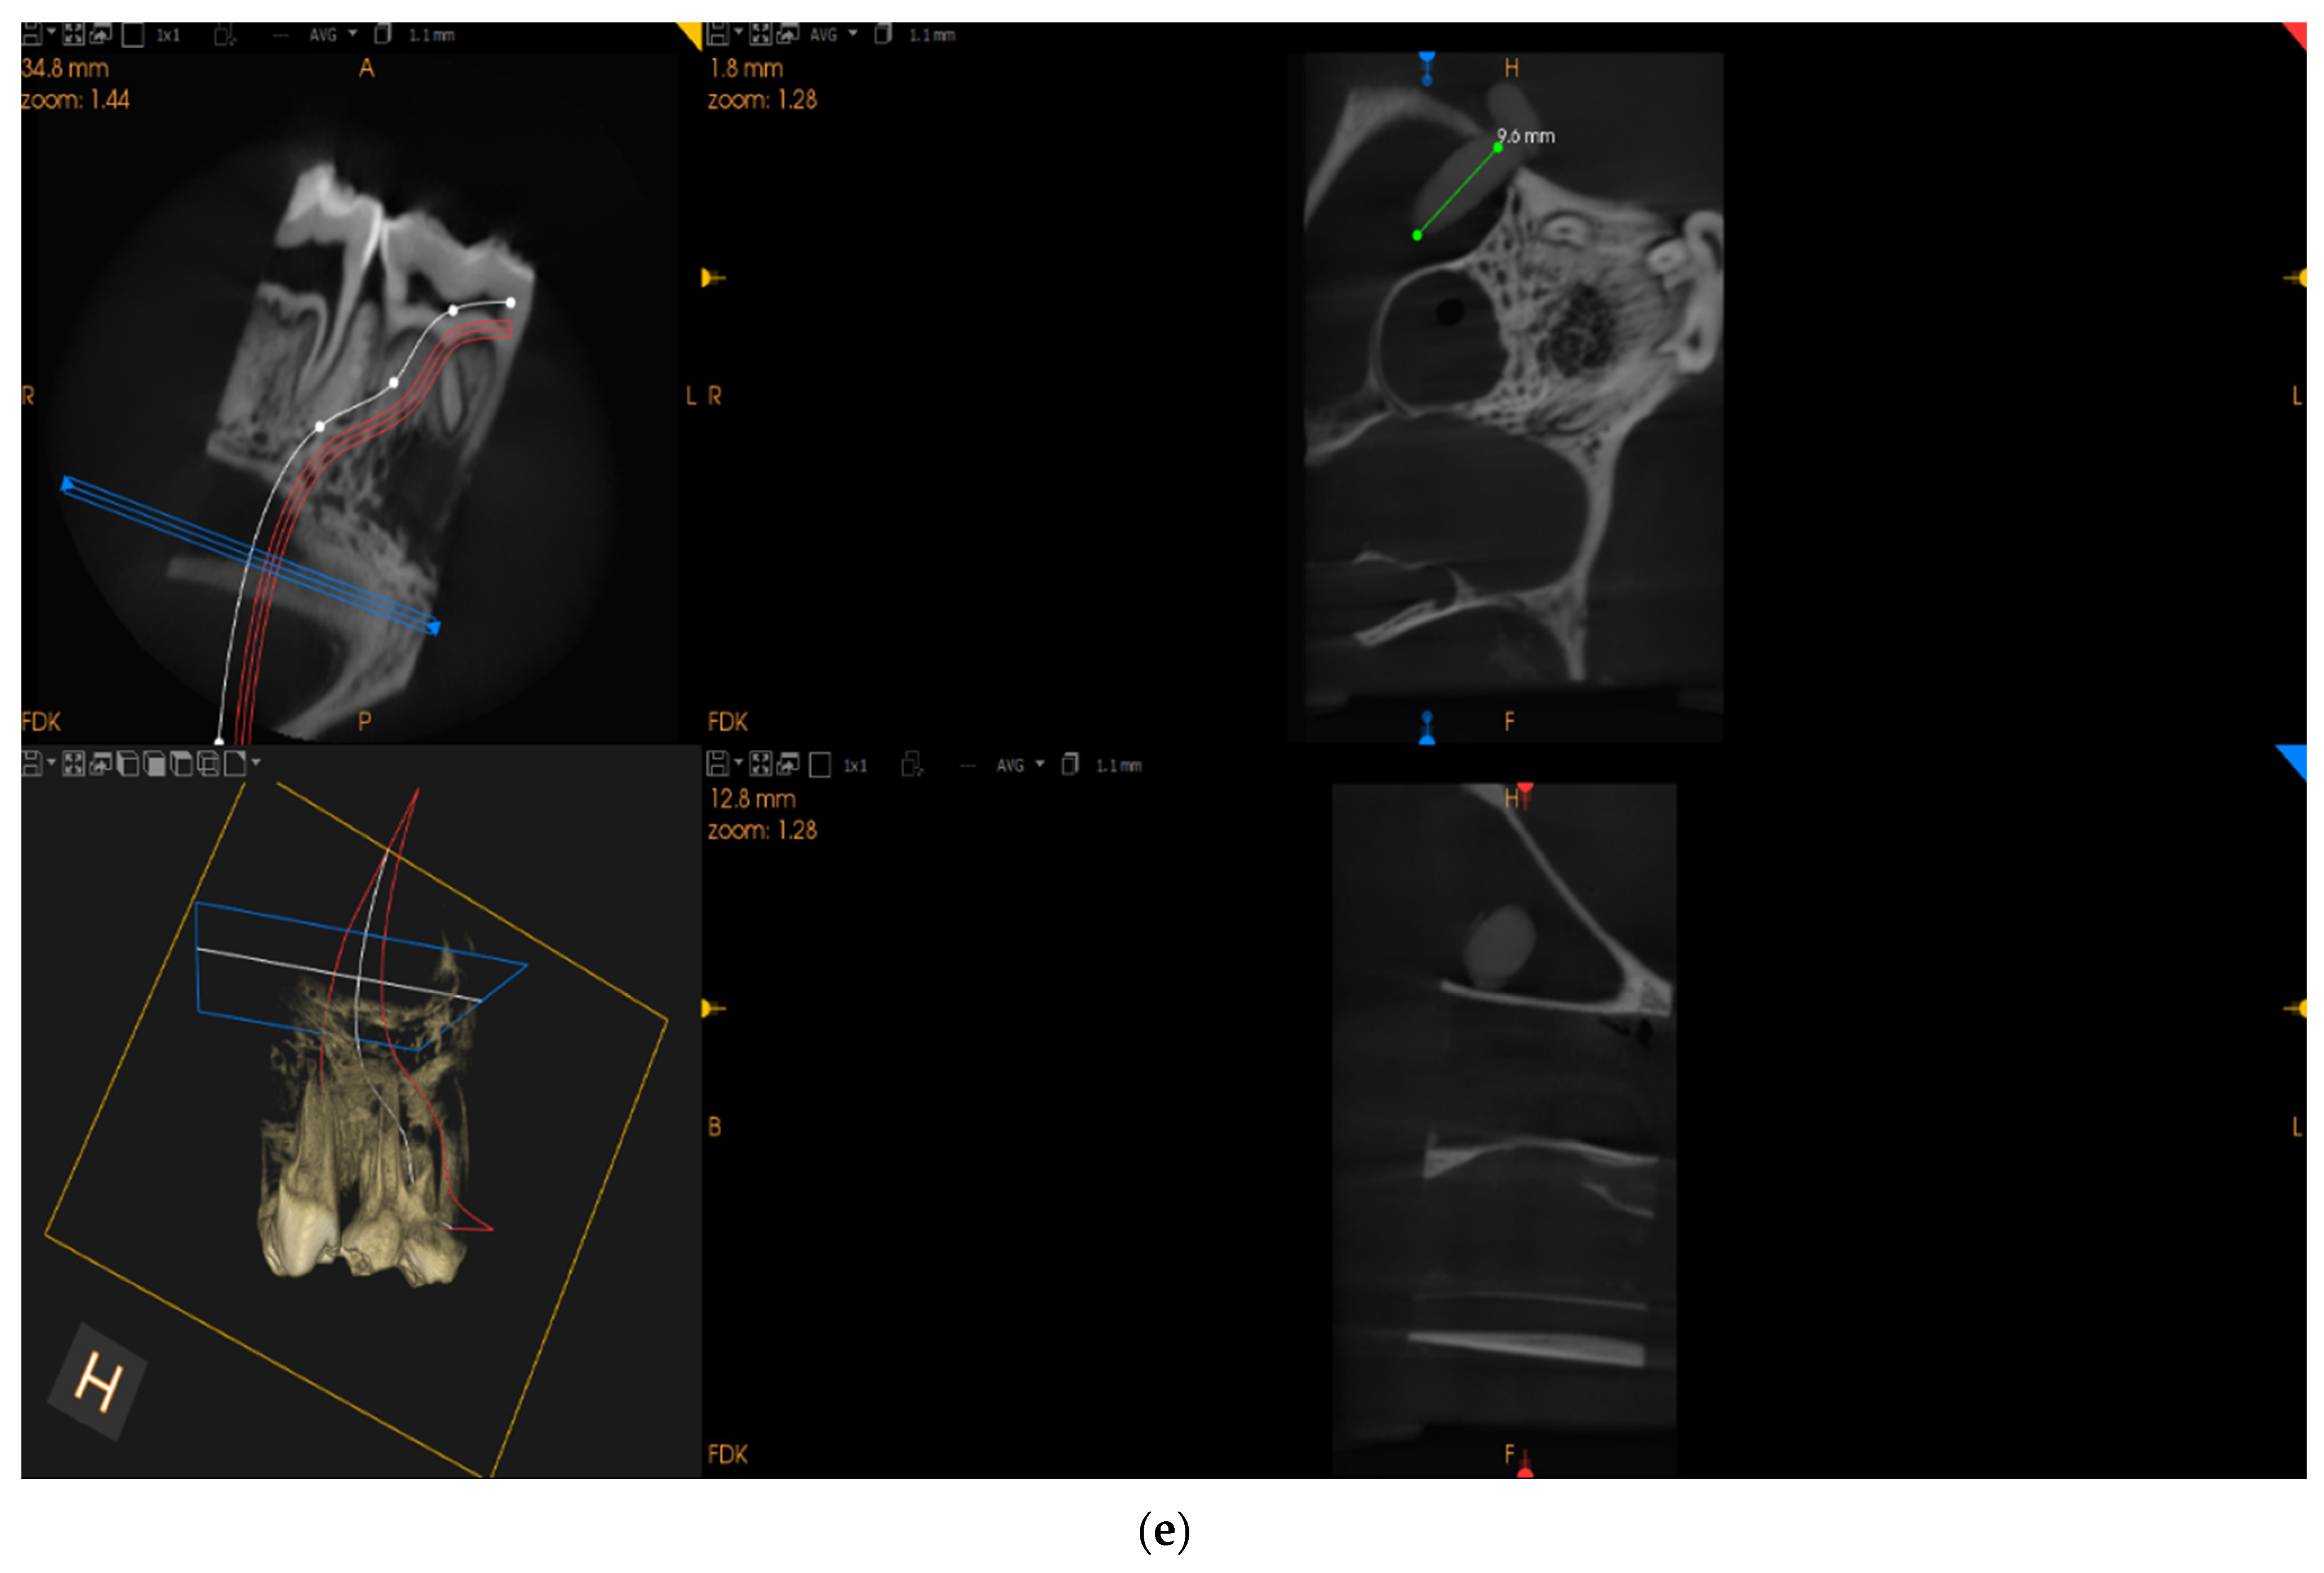

- Staining: The sections were stained using Goldner’s Trichrome, a method that highlights the difference between osteoid (unmineralized bone) and mineralized bone, as well as providing insights into the cell morphology.

- Microscopic Analysis: The stained sections were analyzed using a Nikon digital camera Sight DS-SMC attached to a Nikon Eclipse 90i optical microscope.